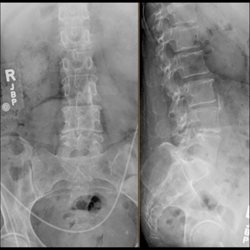

Lumbar Spine Plain Film 3

4 additional plain film studies